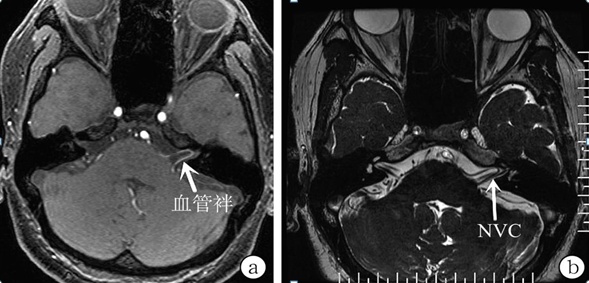

经人介绍,王先生来到上海市同仁医院神经外科就诊。医生详细询问病史,入院完善检查排除了耳源性眩晕可能、心源性头晕可能、颈椎病可能和脑血管病脑缺血性头晕可能,头颅MRTA提示有血管压迫:考虑为体位失能性眩晕,可以通过手术治愈。

治疗需要解除前庭神经的血管压迫才能治愈该疾病,因此只能行微血管减压术才能治愈该疾病。手术治疗前需进行一系列检查排查其他病因的眩晕,具有典型的间断性体位相关的眩晕症状,磁共振检查有明显血管压迫前庭神经。

头颅MRTA提示有血管压迫